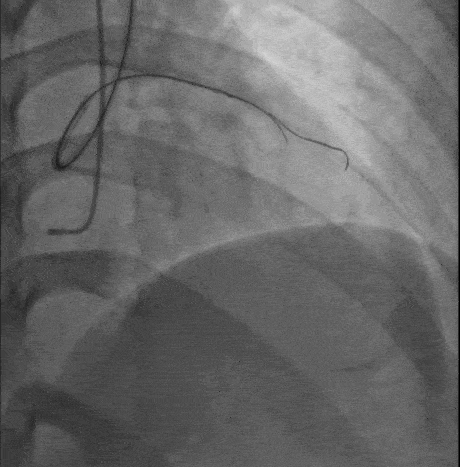

造影

操作过程 XT-R顺利通过第一闭塞段

第二段病变通过困难角度过大更换XT-A仍通过失败 交换双腔微导管+Gaia-2

Gaia-2进入内膜下微调进入真腔交换工作导丝进行IVUS检查